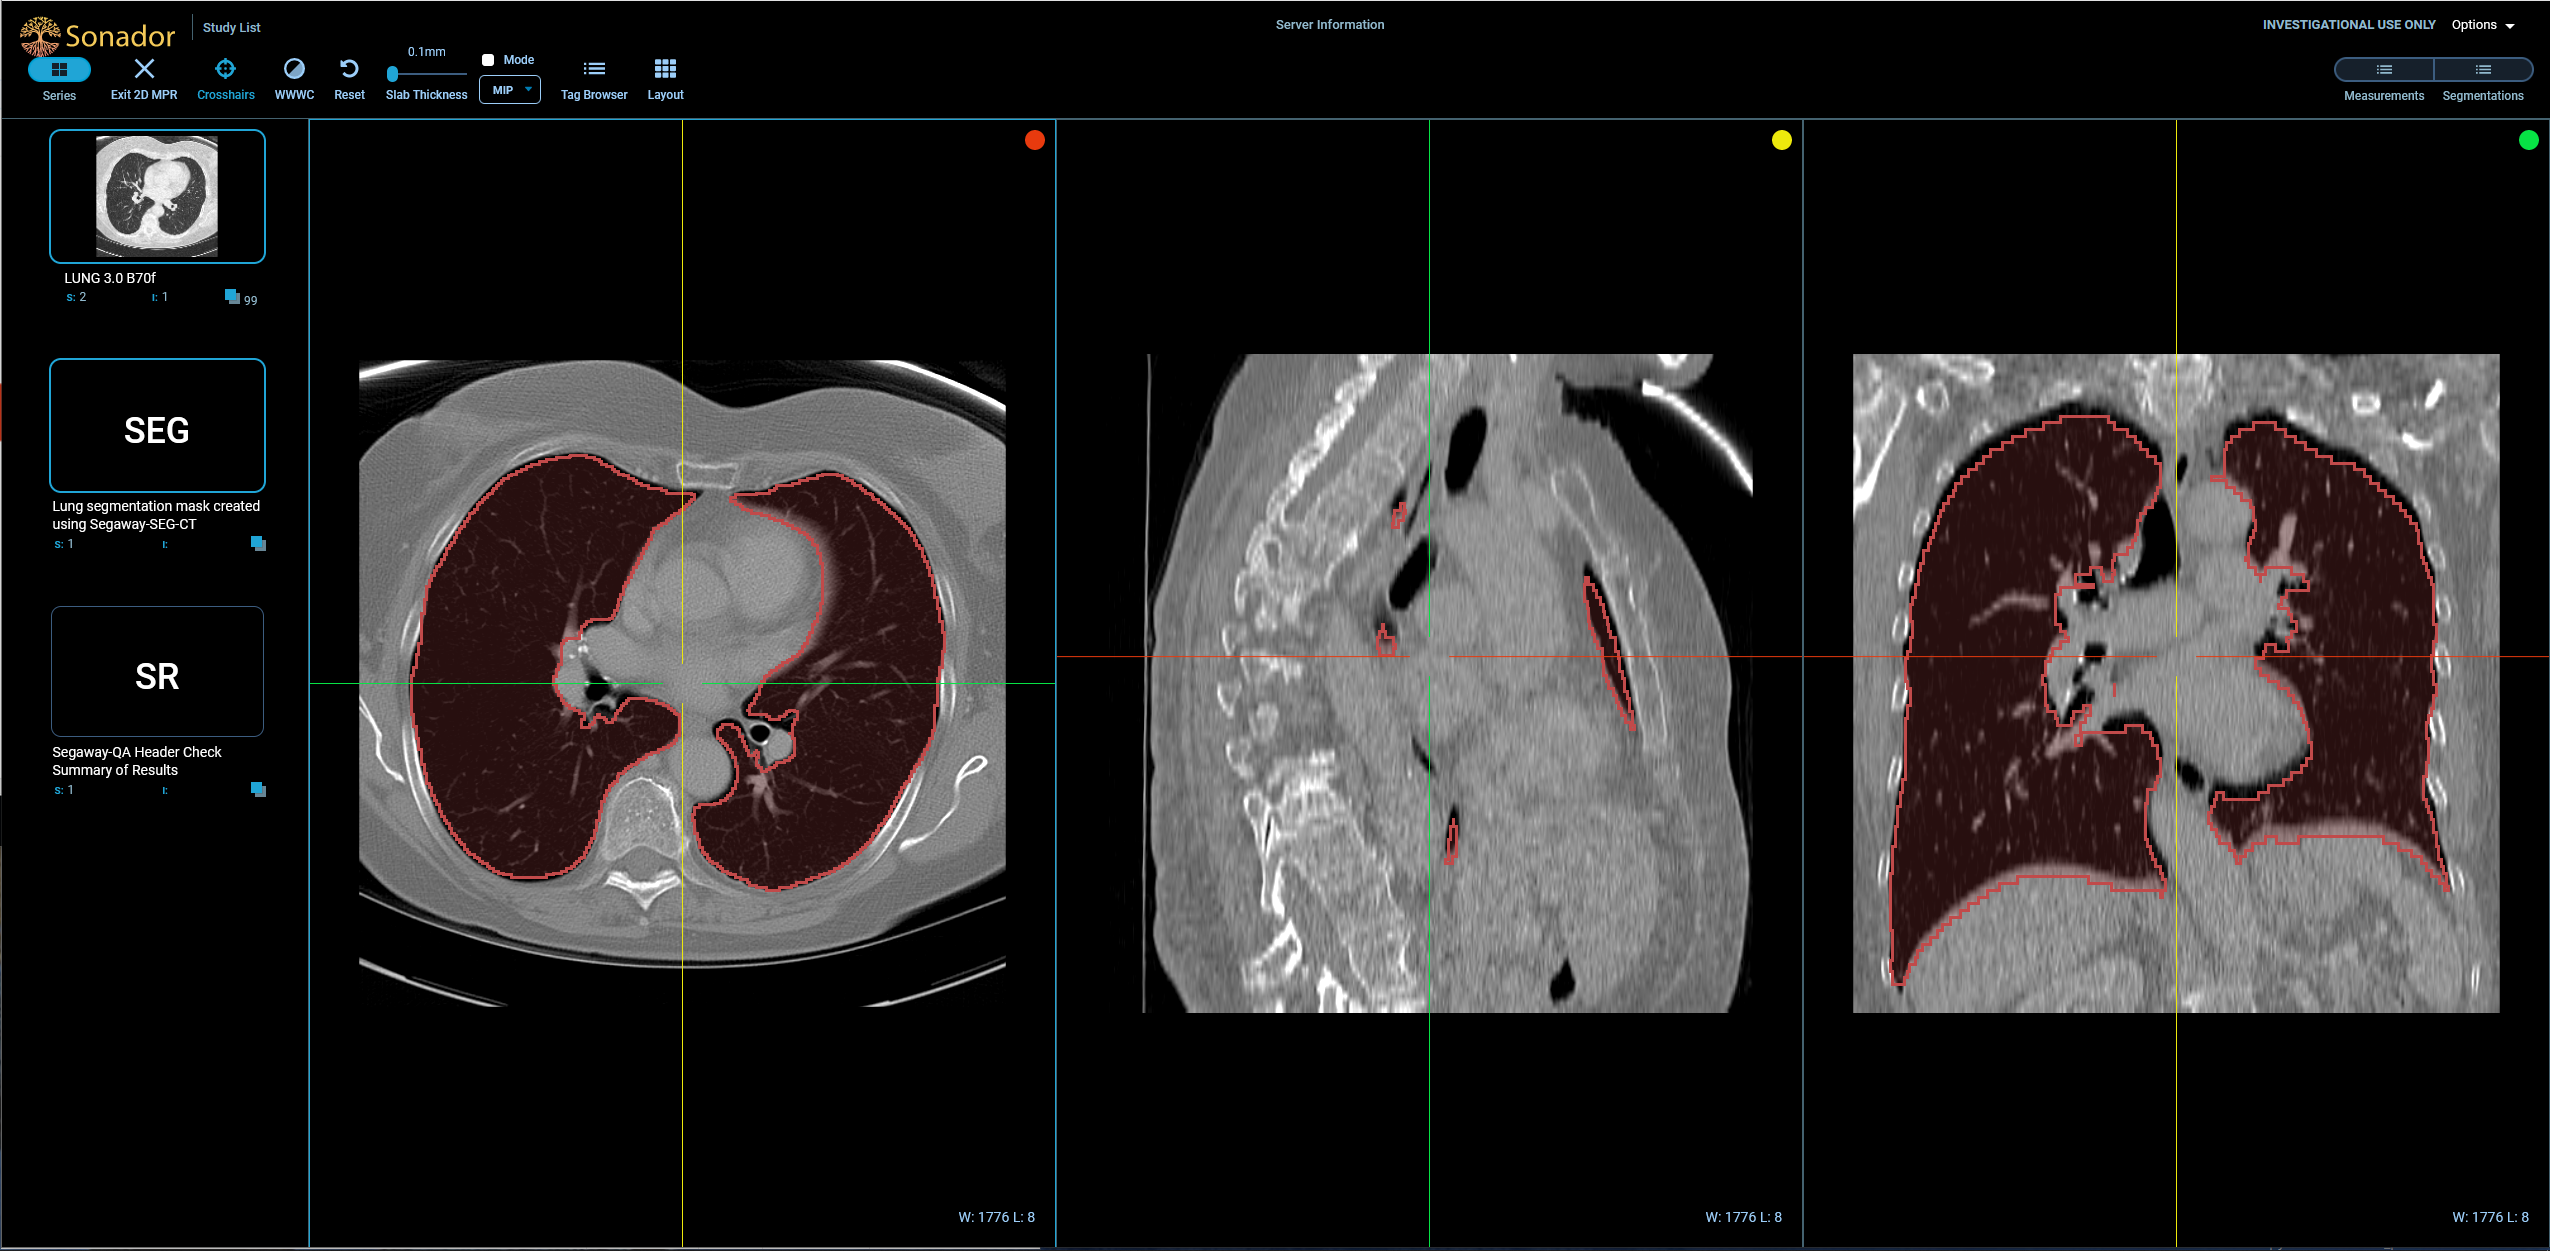

Once you have completed all instructions in the notebook, you can view the example CT study by opening http://imaging.local:8070 in your browser (or refreshing the page if you already have it open) and clicking on the C3N ... row in the "Study List."